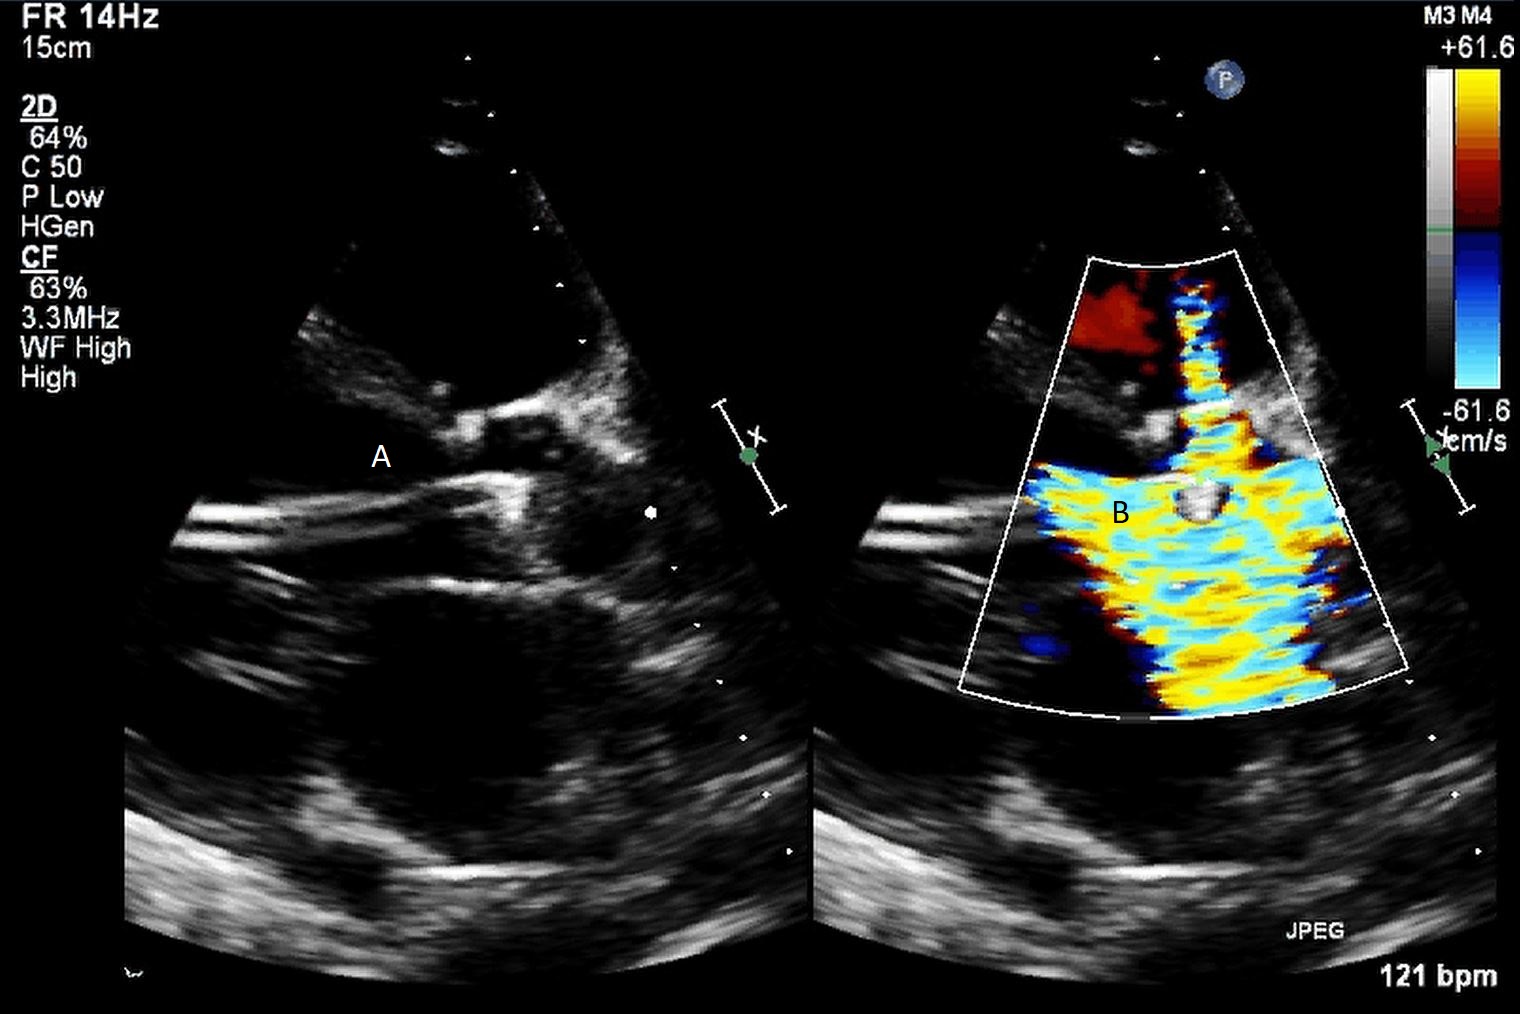

Fig. 7.A parasternal long axis view on a transthoracic echocardiogram. The distance from the Impella inlet to the aortic valve is measured and noted to be 3.9 cm. (A) LV Cavity. (B) Impella. (C) Ascending aortic root.

Fig. 8.A parasternal long axis view on a transthoracic echocardiogram zoomed up on the aortic valve. Color flow imaging demonstrates a mosaic pattern at the Impella outlet, confirming its position as being above the aortic valve. (A) Impella outlet. (B) Mosaic pattern at Impella outlet on color flow doppler.